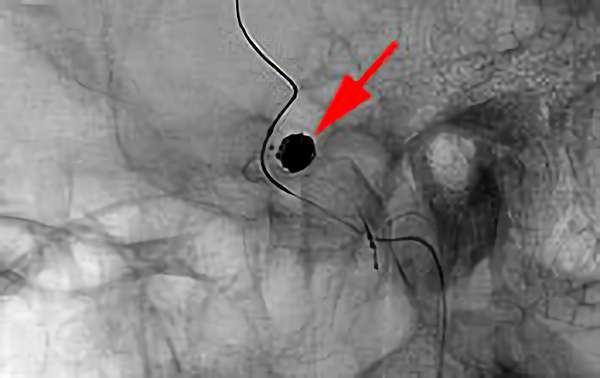

No.1628 手術中